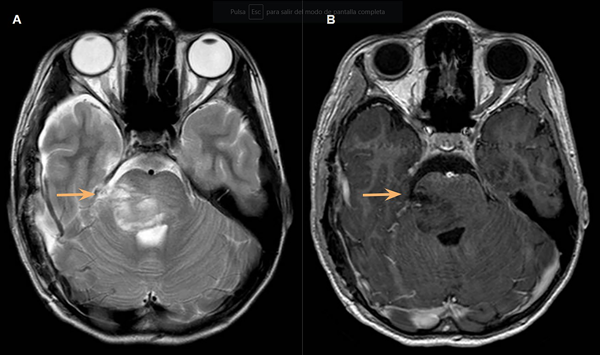

Se decidió en conjunto con el equipo de oncología realizar la biopsia quirúrgica mediante un abordaje subtemporal, de la cual se enviaron 4 fragmentos de aproximadamente 0.5 cm x 1 cm. La anatomía patológica concluyó glioma difuso de la línea media H3 K27-alterado (grado 4 de la OMS). (Fig. 3C-D). La paciente cursó 2 días de internación en unidad de terapia intensiva con posterior traslado a sala general donde se otorgó el egreso sanatorial al cuarto día postoperatorio, sin presentar complicaciones. La paciente realizó radioterapia y se encuentra en seguimiento por oncología. (Fig. 4A-B).

Fig 4: RMN control realizada a los 3 días postoperatorios, secuencias T2 y T1 con contraste. El sitio de biopsia se puede evidenciar con la flecha naranja.